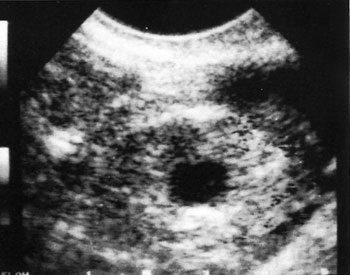

Εικόνα 2. Διακολπικός υπερηχογραφικός

έλεγχος έκτοπης κύησης.

Η υψηλής ανάλυσης εικόνα της διακολπικής κεφαλής προσφέρει καλύτερη εικόνα της

ενδομήτριας κοιλότητας, των εξαρτημάτων και των ωοθηκών. Το διακολπικό υπερηχογράφημα

αποκαλύπτει την ενδομήτρια κύηση μια εβδομάδα νωρίτερα, έναντι της διακοιλιακής

προσέγγισης. Πράγματι, μερικές μελέτες έχουν δείξει ότι το κύριο σημείο στο

οποίο υπερτερεί το διακολπικό υπερηχογράφημα έναντι του διακοιλιακού, είναι

ο πιο ακριβής προσδιορισμός των ενδομήτριων, παρά των έκτοπων ευρημάτων.